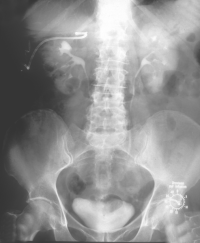

Die Patientin wurde beim Urologen wegen seit 3 Wochen persistierender Flankenschmerzen rechts vorstellig. Der Untersuchungsbefund zeigte als Auffälligkeit ein klopf- und druckschmerzhaftes Nierenlager rechts. Der Urinstatus wies keine Besonderheiten auf. Sonographisch fand der Urologe eine ca. 11 cm große einfache Nierenzyste rechts, die bis in das Nierenbecken reichte. Mit dem anschließend durchgeführten i.v.-Pyelogramm konnte eine Abflussbehinderung aus dem Nierenhohlraumsystem ausgeschlossen werden. Es waren jedoch glatt berandete, zystentypische Kelchausziehungen der oberen und mittleren Kelchgruppe zu erkennen. Der Urologe stellte die Patientin stationär in der Klinik vor. Zum Ausschluss eines eventuell vorliegenden zystischen Karzinoms wurde ein CT des Abdomens durchgeführt. Hier fand sich eine große, unkomplizierte Zyste, die die Niere verdrängte (Abbildung 4).